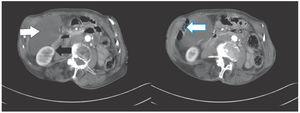

Mujer de 82 años de edad, que durante los 10 años previos presentaba dolor abdominal recurrente e intolerancia a la vía oral. En el último año se agregó pérdida de peso de aproximadamente 10 kg y una masa abdominal en flanco derecho, con aumento progresivo de tamaño. Al examen físico se palpó masa de aproximadamente 10 cm por 8 cm, móvil, indurada, de bordes irregulares. El ultrasonido (USG) abdominal mostró una lesión quística hipocoeica, multiseptada, ubicada en el cuadrante superior derecho, probablemente dependiente de hígado. La tomografía computarizada (TC) de abdomen mostró una lesión quística de aproximadamente 14 cm, de aproximadamente 14 unidades Hounsfield (UH) por debajo del hígado y delante del riñón derecho, condicionando desplazamiento del colon derecho (Figura 1). Se realizó una laparotomía exploradora, encontrando un tumor quístico retroperitoneal, adherido al mesocolón transverso y páncreas, el cual midió 15 cm por 10 cm por 5 cm. La pared del quiste era blanquecina y muy vascularizada (Figura 2). La lesión fue resecada completamente y su evolución sucedió sin complicaciones por lo que fue egresada por mejoría. El examen histopatológico confirmo un linfagioma retroperitoneal (Figura 3).

¿ Figura 1. TC de abdomen que muestra una lesión retroperitoneal quística por debajo del hígado (flecha blanca), delante del riñón derecho (flecha negra) y por detrás del colon derecho, (flecha en marco azul) de aproximadamente 14 cm por 12 cm y 14 UH.